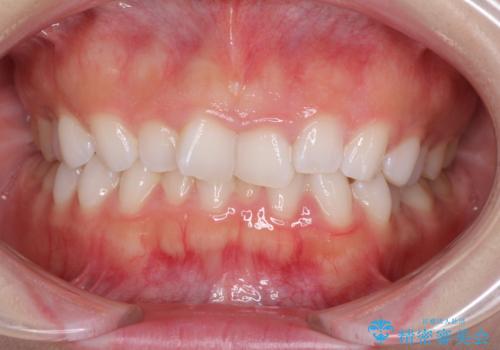

デコボコと深い咬み合わせの改善 インビザラインによる矯正治療

- 口元のデコボコと深い咬み合わせ(ディープバイト)を気にして来院された患者様です。

インビザラインによる上下歯列の拡大と、IPR(歯と歯の間を削る)にるスペースの獲得により、口元のデコボコとディープバイトを改善することとしました。

インビザラインは、装着していない時間がどれだけ短いかが、治療期間を大きく左右します。こちらの患者様は1日22時間以上、毎日欠かさず装着してくださったため、1年強という短期間で満足のいく歯列に整えることができました。